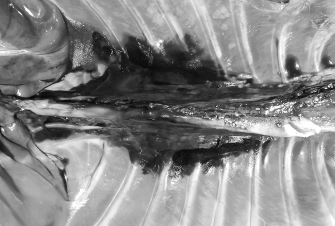

Fig. 2. Dorsal view of the thoracic cavity of a cat cadaver after a polyurethane foam injection after the removal of hepaxial and intercostal muscles. Despite the longitudinal subpleural spread, the foam surrounds the intercostal nerve only at the level of needle insertion site (arrow) and not at the adjacent spaces. The forceps are used to emphasize an intercostal nerve running above the endothoracic fascia, which appears almost completely intact in this subject.

During the preliminary phase, after post-injection anatomical dissection of the epaxial and intercostal muscles, the foam was observed to be directly in contact with the spinal nerves only at the level of the needle insertion site and not at the adjacent spaces. Cranially and caudally to the insertion point, in fact, the foam and the spinal nerves appeared separated by a thin connective layer identified as the endothoracic fascia (Fig. 2). The observed foam spread was identical between the two techniques used in this phase, and the surrounding connective tissues were intact. These findings allowed us to move to the second phase, assuming that the spread obtained after probing the TPVS could be used as a clinical model.